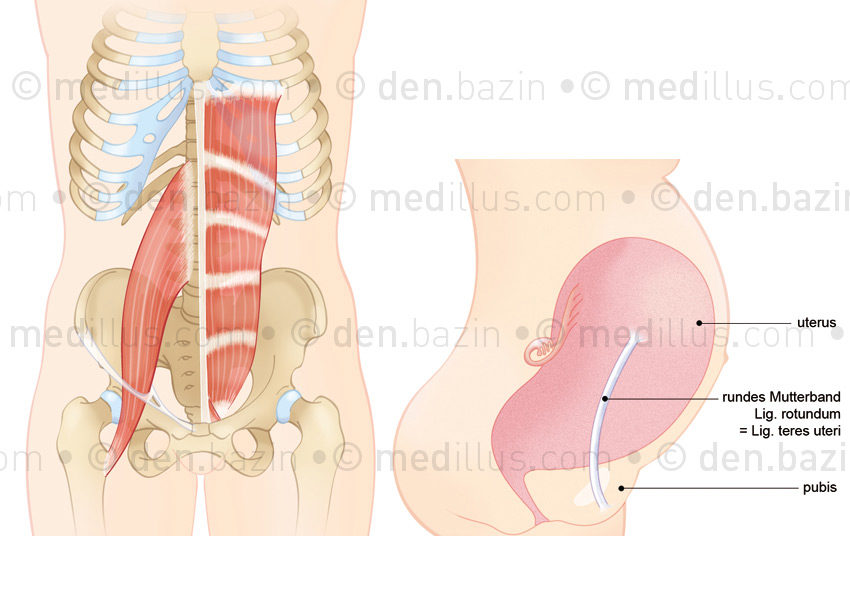

Muscle psoas et abdominaux, ligament rond